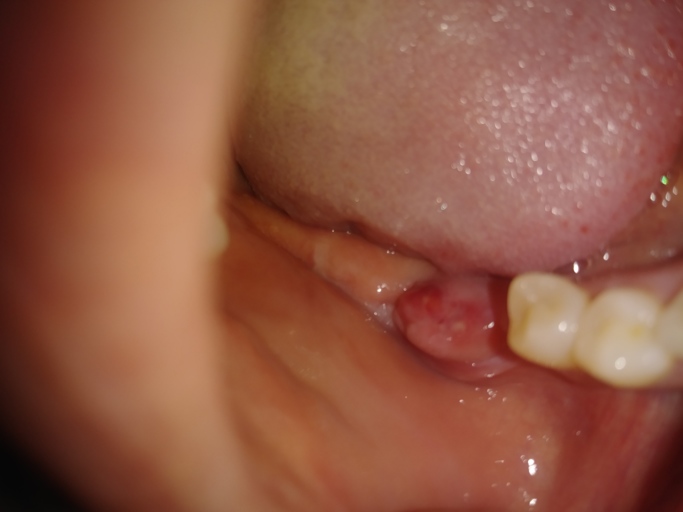

I had a tooth pulled and I got dry socket now I have a lump that seems to have a head on it.. I am taking antibiotics clindamycin 300mgx3daily. The pain is gone in my jaw but the lump is sensitive.I go back to my dentist saturday. But I am so worried about this now. Is there any way to so you a picture? I am alergic to penicillin and. I have dental anxiety. I just want to know if it is an abscest. It has not grown any but it also has not srunck. But my tongue it feels about the size of a marble. Can you get an abscest from dry socket?

The picture submitted appears to be the tissue healing. It can be sore, tender, and swollen during this process. It is hard to see if there is a suture, however as long as you are keeping it clean, free of debris, and taking your antibiotics as directed, you are doing everything you can to avoid an infection. The pain subsiding is a good indication that the area is healing. Continue to be cautious until you have had clearance from the surgeon to resume regular activity and resume a normal diet. Having an abscess form after the tooth removed is possible, but not likely if you are following your post operative care instructions and taking your antibiotics as directed.